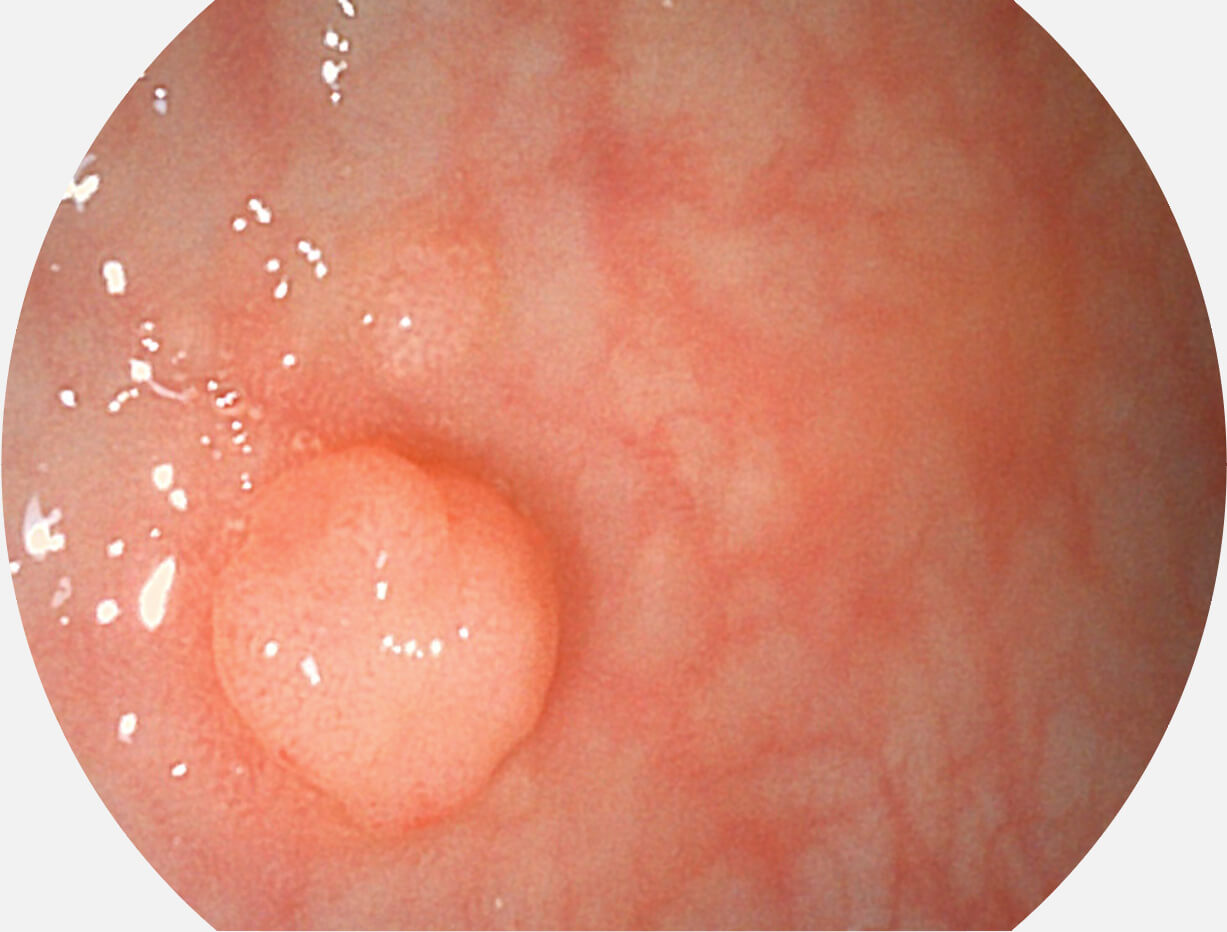

助力消化道早期疾病诊断

图像具有高亮度、高黏膜血管颜色对比度的特点,且不改变粘液、食物残渣、粪便的基本颜色,可在中远景下进行观察,助力消化道早期疾病的诊断。